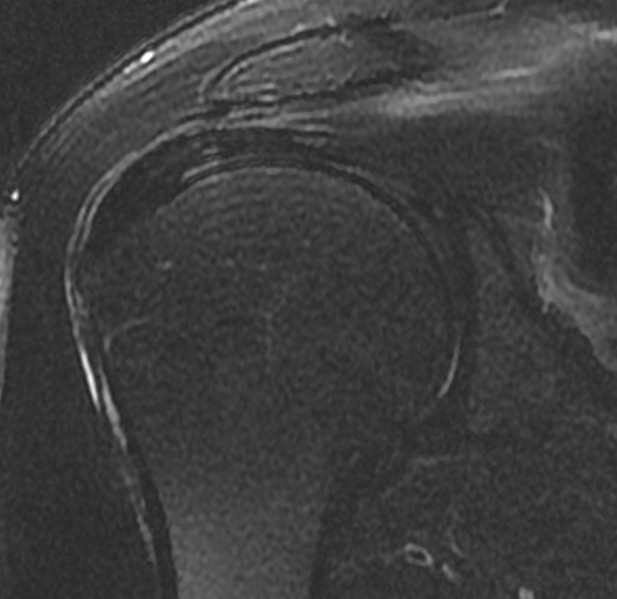

수개월간 지속되는 우측 어깨통증으로 가까운 병원에 내원해서 엑스레이,초음파 검사상 회전근개 부분파열, 염증, 석회로 진단받고 꾸준한 보존적 치료를 시행함. 재생주사치료,충격파치료,도수치료를 꾸준히 시행하였으나 증상이 호전되지 않고, 치료시에만 잠깐 괜찮다가 다시 아프기를 반복. 점차 팔을 조금만 움직여도 통증이 심해지며, 특히 팔을 옆으로 들때나 뻗을때 뒤롤 돌릴때 통증이 심해지고, 밤에도 통증이 시작됨. 시술전(pre) MRI 검사상 회전근개 내측에 부분파열이 관찰되며, 힘줄염이 동반된 상태로 힘줄이 헤지고, 약해진 상태로 진단받고 더핌스 축소봉합술을 시행함. 시술후(post) 시행한 검사에서 약해졌던 힘줄이 정상힘줄로 회복된것이 확인되며, 시술후 바로 일상생활로 복귀하였으며, 어깨를 움직일때 아프던 통증과 야간통이 사라짐